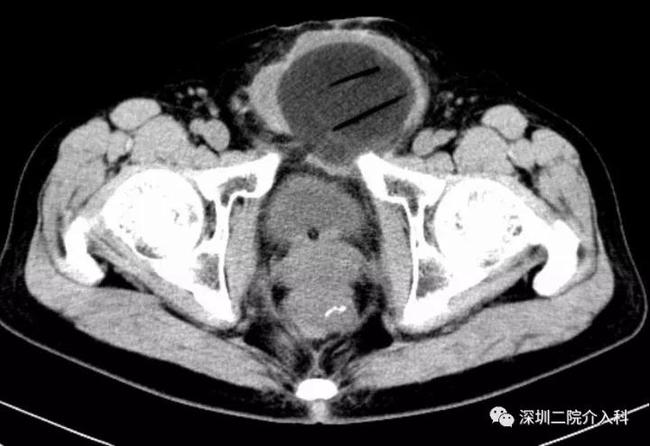

图示CT引导下,经过精密计算肿瘤大小及消融范围后,分别置入4根冷刀: